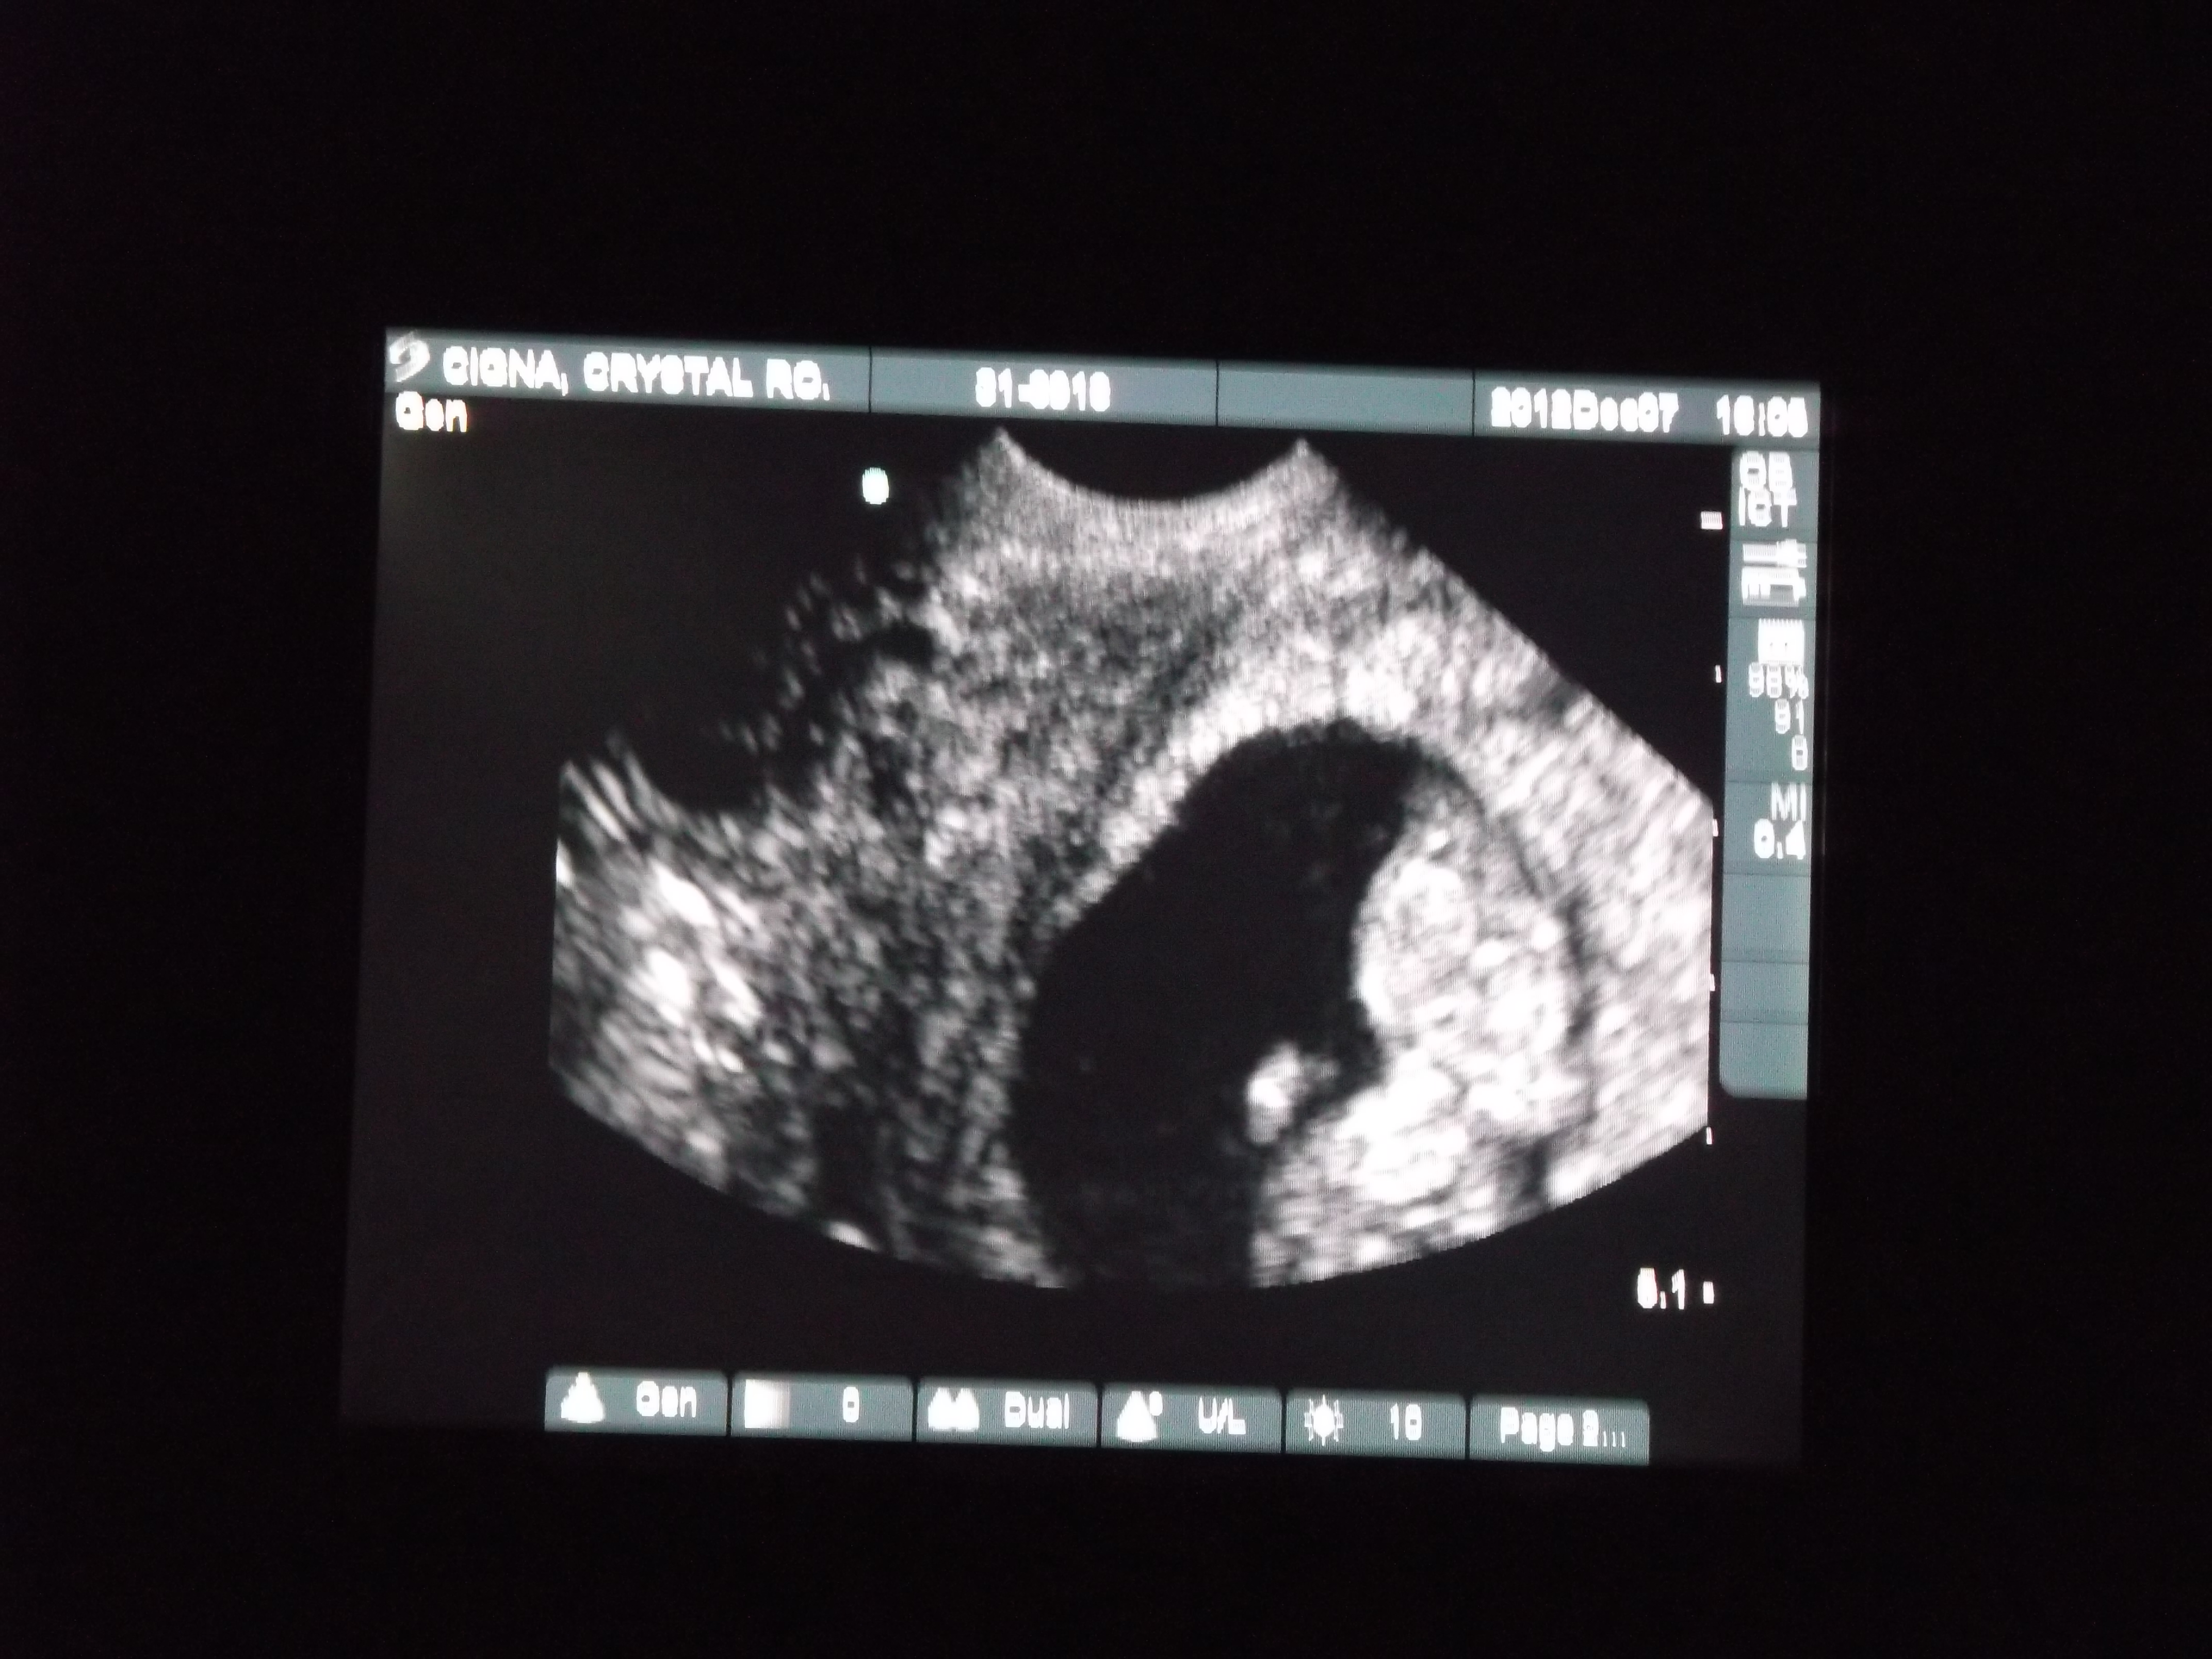

Attachment 7108

No way to tell from this image. Do you have a side profile image?